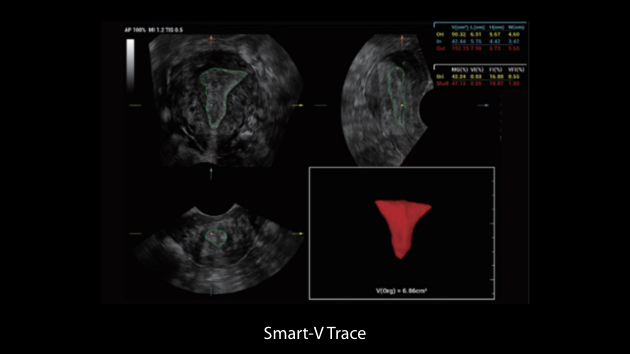

Obrazy kliniczne